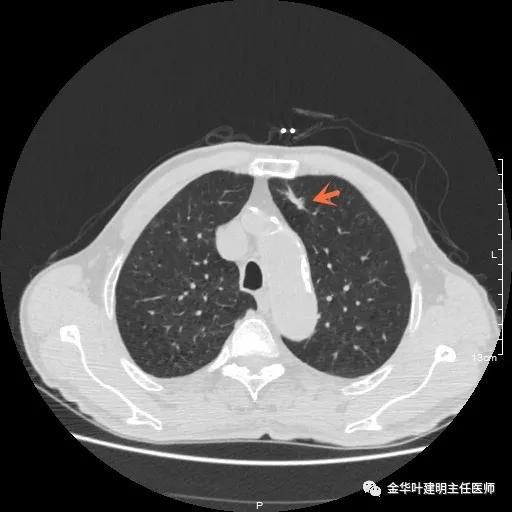

以上示右中叶病灶4。也是囊腔型病灶,病灶大,囊壁是磨玻璃密度,亦是较为典型的囊腔型肺癌影像。单病灶看,需中叶切除来治疗,因病灶3的存在,中叶切除可同时解决病灶3与病灶4。